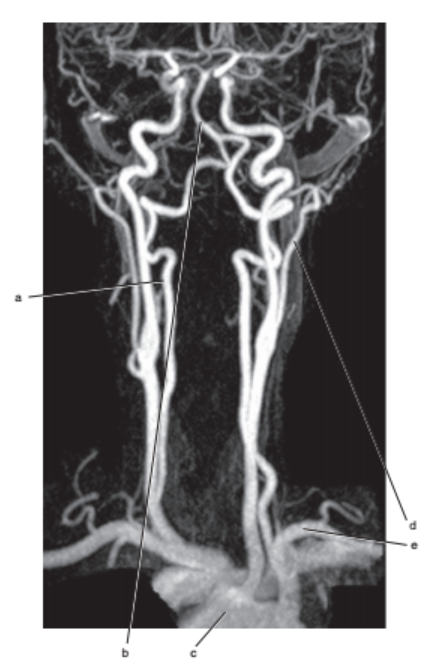

What is letter l ?

Common carotid

What is letter e ?

Subclavian artery

What is letter f ?

Common carotid artery

Vertebral artery

Basilar artery

Carotid sinus/bifurcation